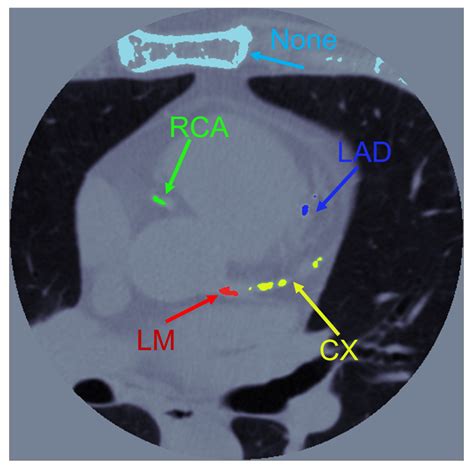

Coronary Artery Calcium scoring is a specialized type of computed tomography (CT) scan that focuses on the heart. Unlike traditional CT scans, CAC scoring specifically looks for calcium deposits in the coronary arteries. These deposits are a sign of atherosclerosis, a condition where plaque builds up in the arteries, narrowing them and increasing the risk of heart attacks and strokes.

During a CAC scan, the patient lies on a table that slides into a CT scanner. The scanner takes multiple X-ray images of the heart from different angles. A computer then processes these images to create a detailed picture of the coronary arteries. The amount of calcium in the arteries is measured and given a score, known as the Agatston score.

The Agatston score is a numerical value that indicates the amount of calcium in the coronary arteries. The higher the score, the greater the risk of heart disease. Here is a general guide to interpreting CAC scores:

• coronary artery calcium score interpretation